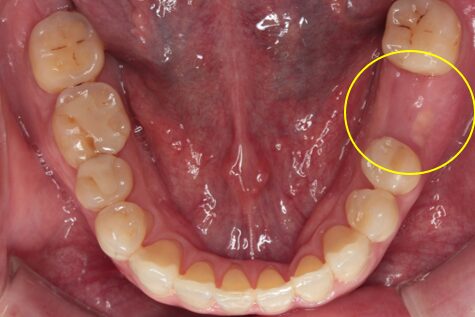

52歳症例